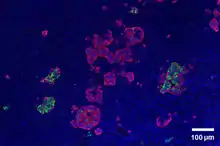

Pancreatic Polypeptide From a Mouse Cell

Through different microscopy techniques, the structural related details of PP cells have been able to be better understood. This is inclusive of how big they are, what their cellular membranes look like, the proteins associated with them, and even their size. PP cells are elongated cells. Another one of these details can be noted in insulins secretory granules, or container like buds, that store insulin within a cell. In PP cells, the size of the insulin granules are smaller and spherical and similar to those in alpha cells. This is noted in human PP cells, but different animals have been shown to have different sized granules compared to humans, like rodents. In cats and dogs, PP cells have large granules.[8] In rats, PP cells have few granules, similar to humans. In dogs, some PP cells are located in the walls of the antrum of the stomach.[3]